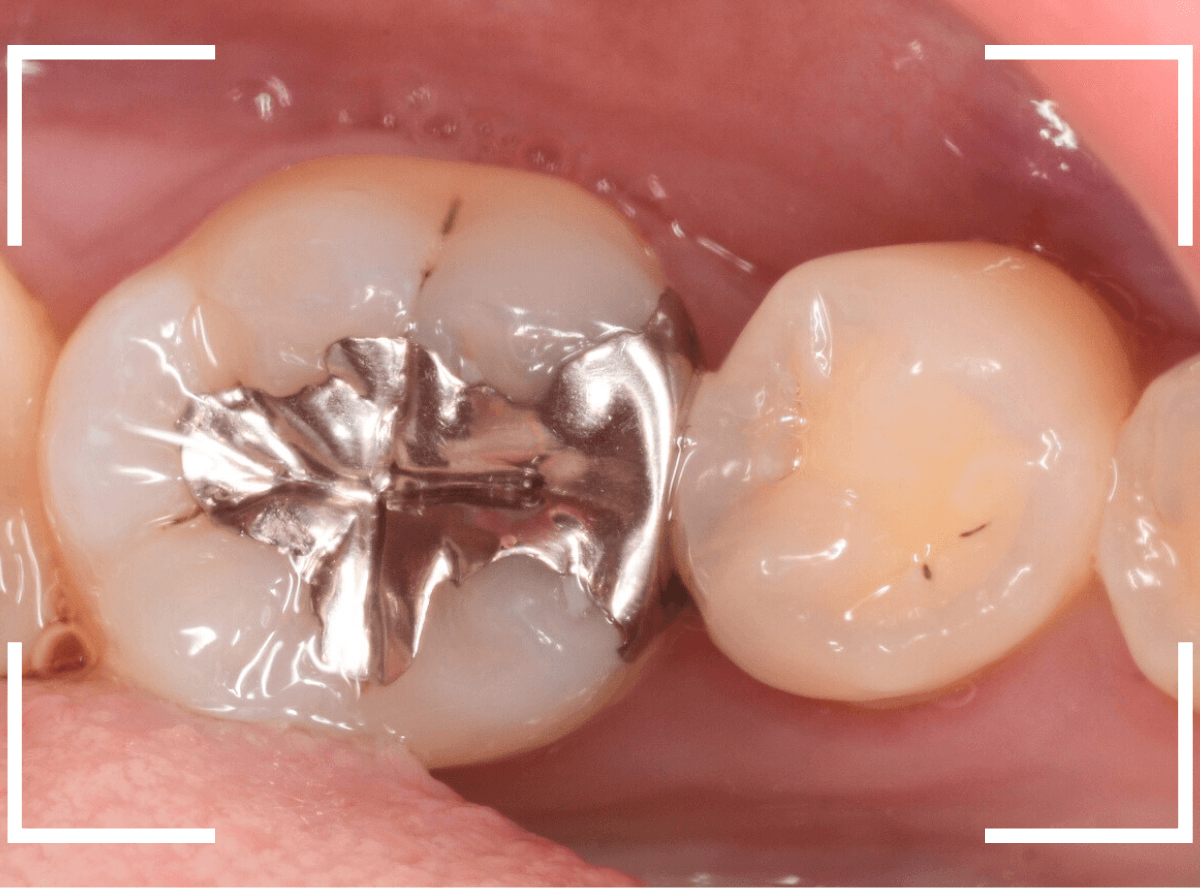

メタル・インレーとメタル・クラウンが入っていますね。

まずは、奥のメタル・クラウンを外します。

メタル・コアが入っていますが、こちらも慎重に外して、中を調べていきます。

レントゲン写真では問題なさそうでしたが、メタルコアを除去すると、中は真っ黒でした。

このように、コアの中で虫歯が進行している場合もありますので、さし歯をやり直す際は、出来る限りコアも外して調べるようにしています。